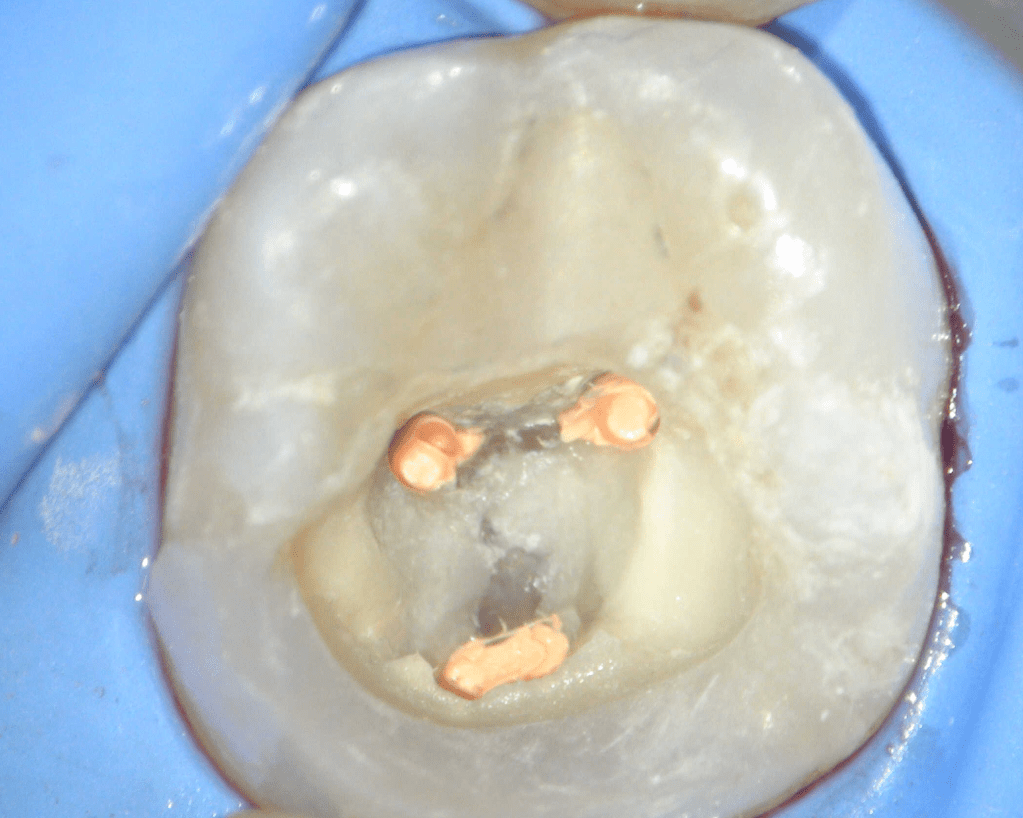

Reco preendo + 4 conductos molar superior